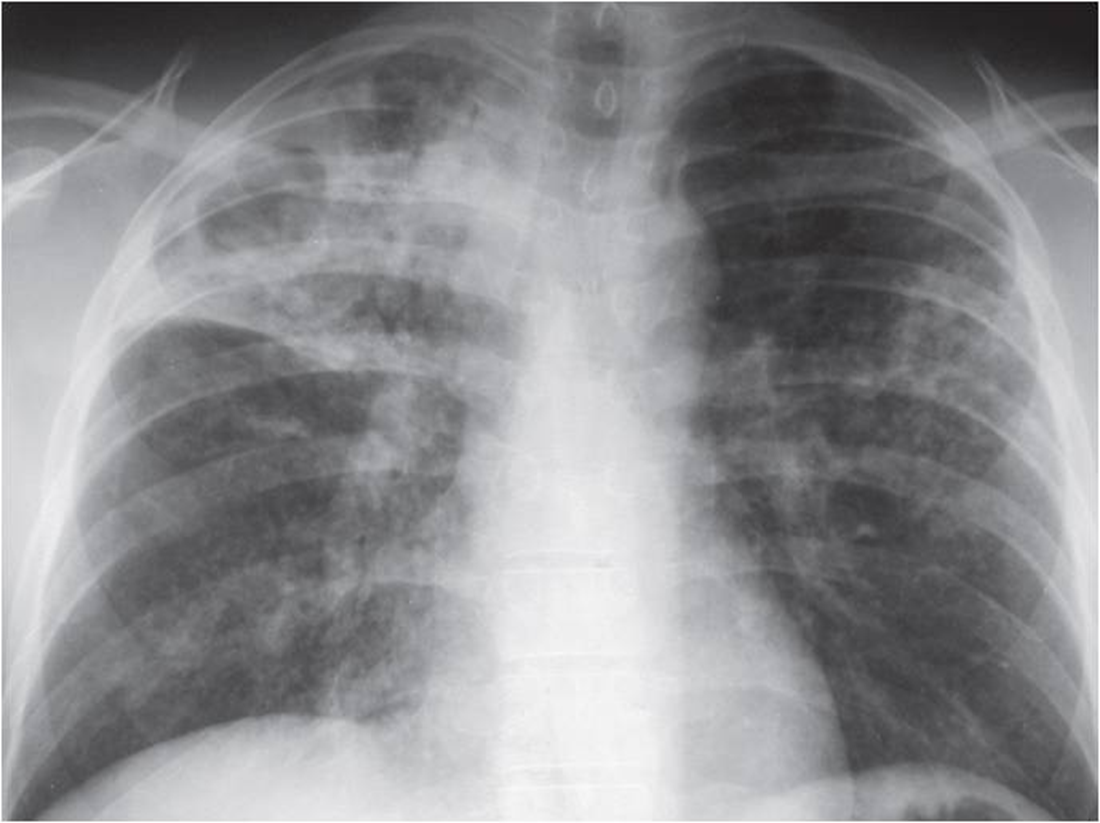

Classic TB radiograph

White in upper lobe and cavities

Reactivation

TB reactivation is more common in ____ ____ lobe

Right upper

TB Disease Case Rate By CXR Classification In Alaskan Natives

RUL some trouble

Infiltrate

Increase risk of disease progressionÂ

No increased risk of disease progression

Cavity in LUL

Even if culture negative is concerning

still concerning